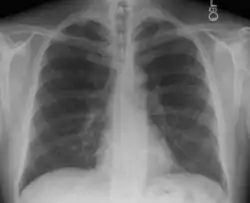

Обработанная цифровая рентгенограмма грудной клетки (лёгочные поля в позитивном изображении, с повышенной контрастностью).